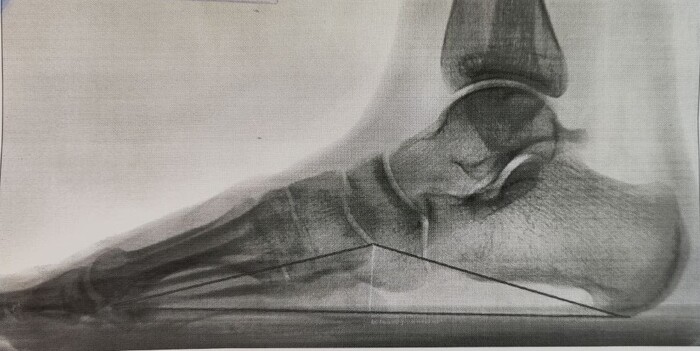

На Р-грамме левой стопы с нагрузкой: в структуре пяточной кости отмечается зона просветления костной ткани размером 29х27х17мм (точные размеры по данным КТ, которая была пройдена призывником),неправильной овоидной формы, с склеротическим контуром, соответствует кисте левой пяточной кости.

По заднему контуру таранной кости визуализируется добавочная кость- os trigonum размером 1.1х1.5см,наиболее вероятно вызывающая импиджмент-синдром заднего отдела голеностопного сустава.

Угол продольного свода левой стопы 160 град., высота 19 мм, соответствует продольному плоскостопию 3 ст. левой стопы.